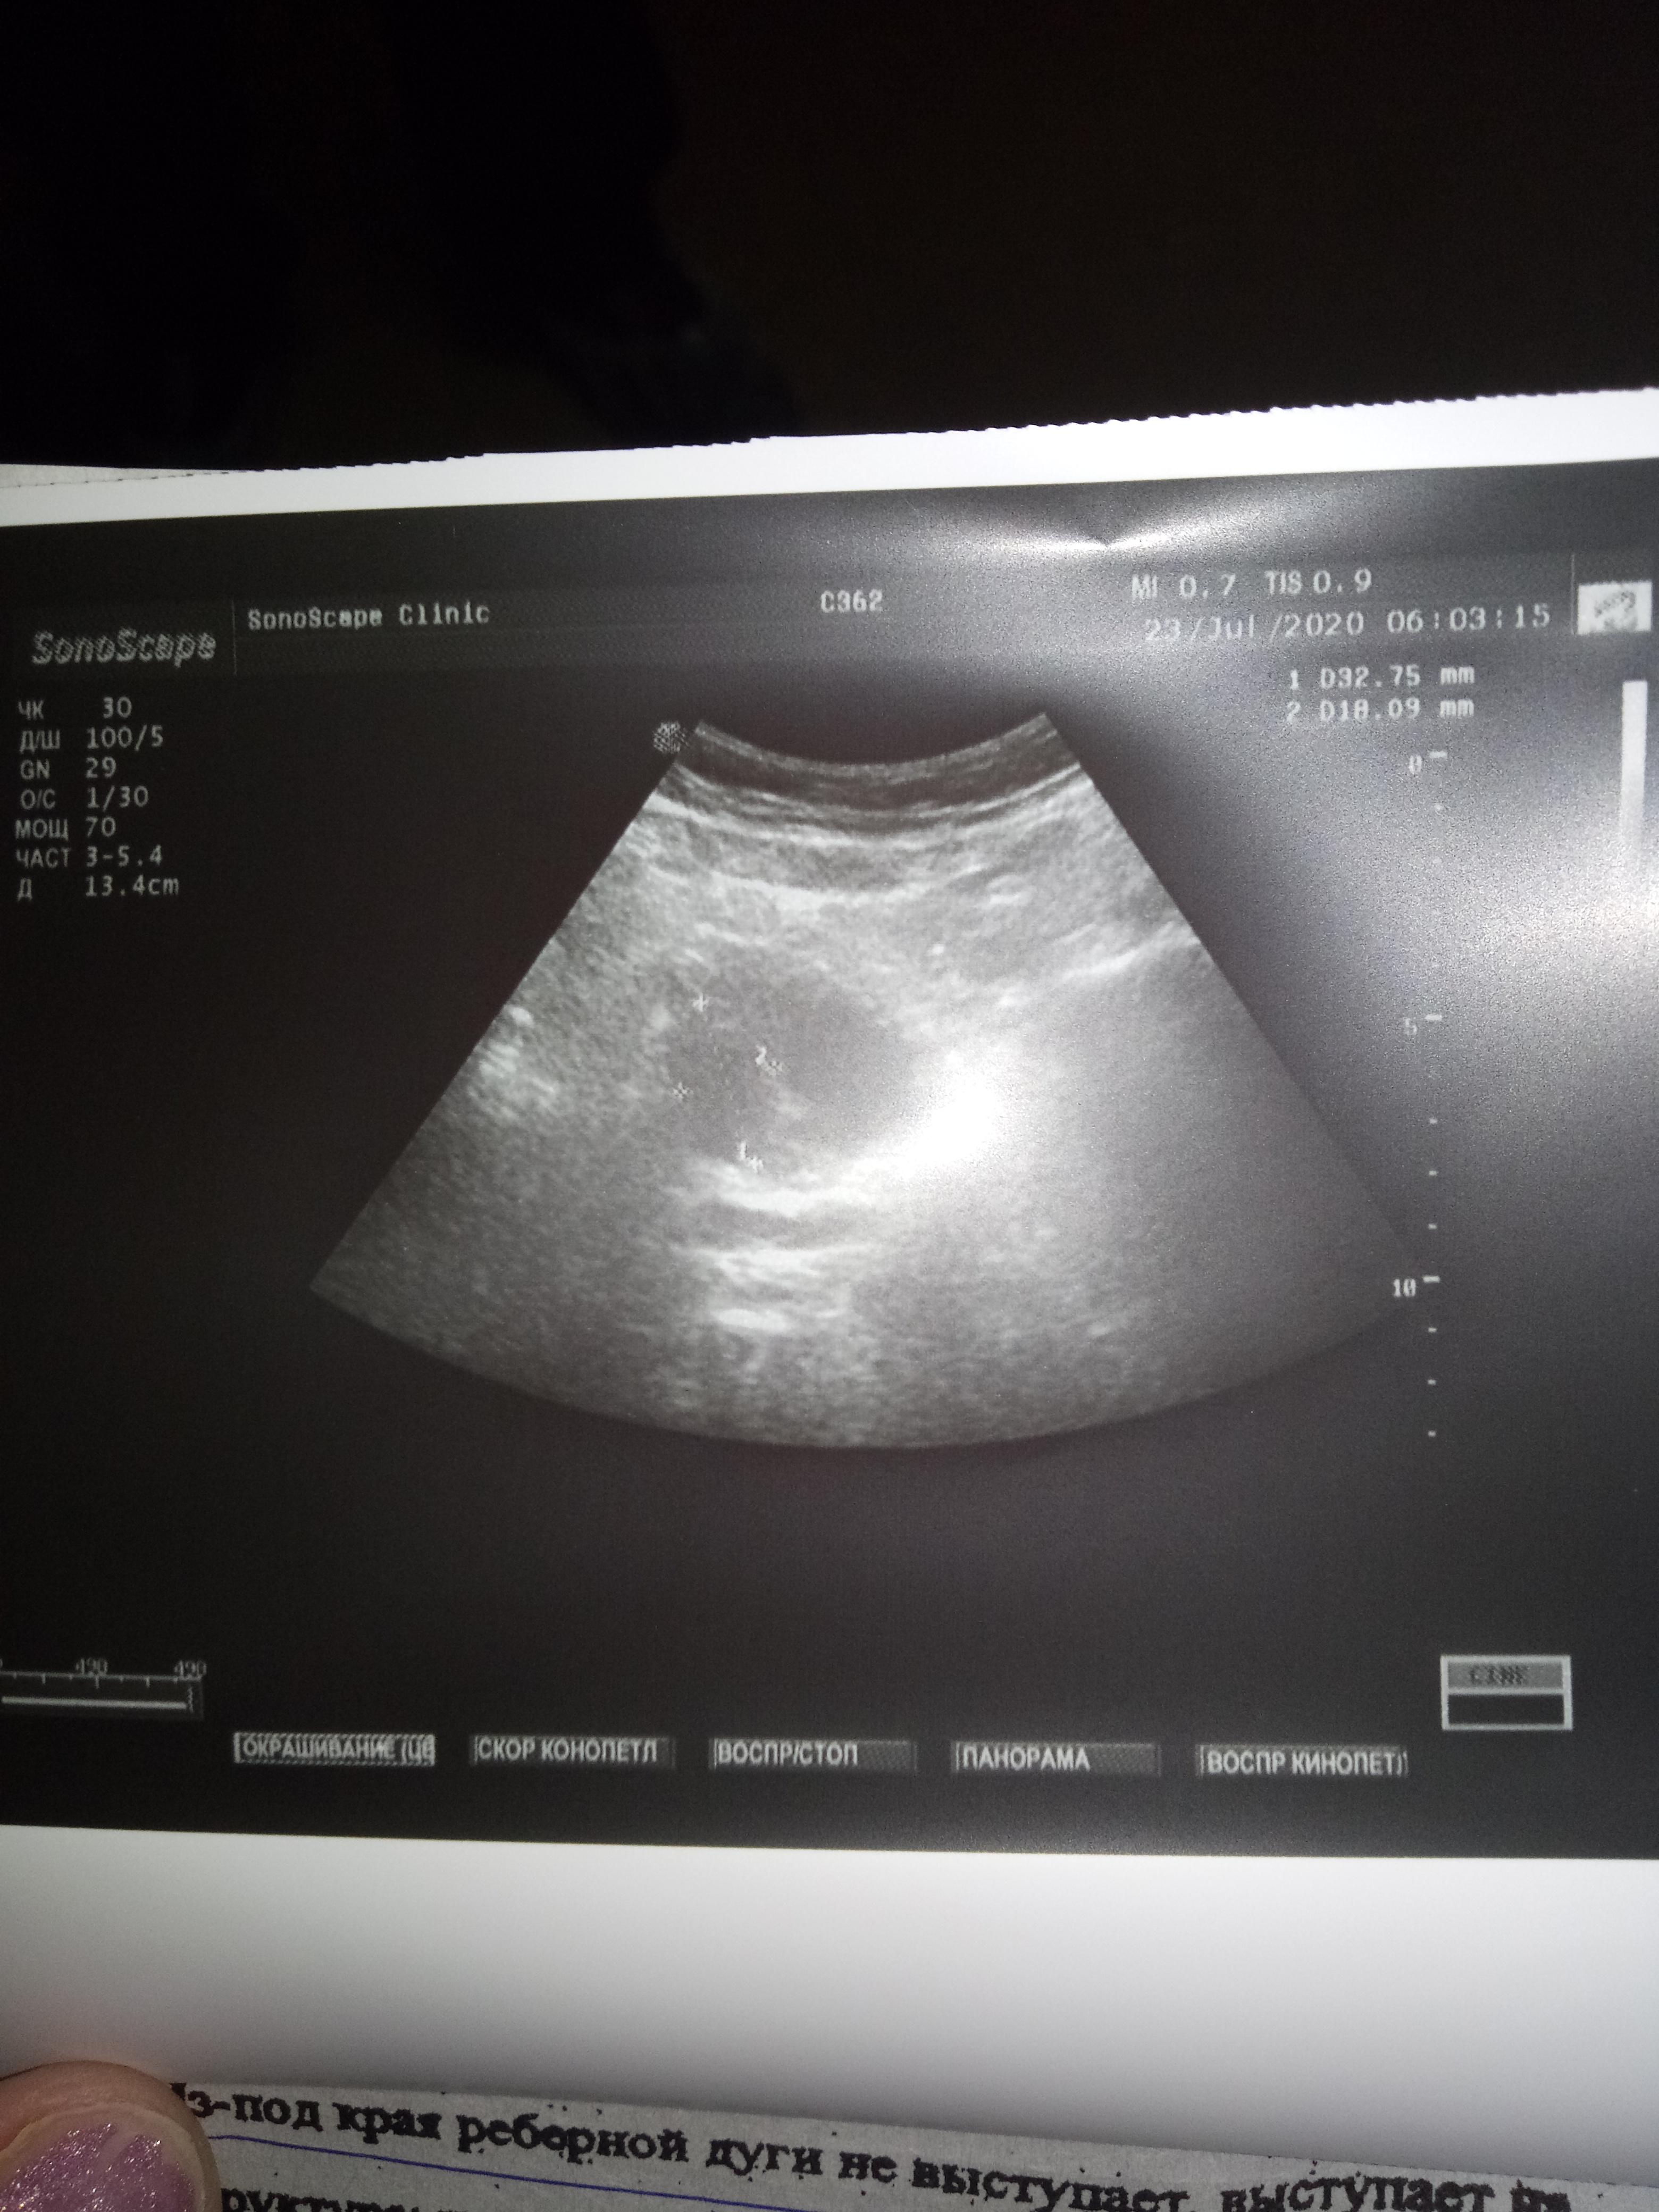

Пожалуйста,можно ли по данным анализам назначить лечение? Какая стадия рака?При отказе на операцию возможен ли прогноз,продолжительность жизни?

анализы отца,пожалуйста подскажите лечение,госпитализироваться отец отказался,боиться.Пожалуйста подскажите лечение,возможно ли оно?